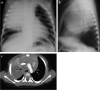

Tuberculosis (TB) remains one of the major public health threats worldwide, despite improved diagnostic and therapeutic methods. Tuberculosis is one of the main causes of infectious disease in the chest and is associated with substantial morbidity and mortality in paediatric populations, particularly in low- and middle-income countries. Due to the difficulty in obtaining microbiological confirmation of pulmonary TB in children, diagnosis often relies on a combination of clinical and radiological findings. The early diagnosis of central nervous system TB is challenging with presumptive diagnosis heavily reliant on imaging. Brain infection can present as a diffuse exudative basal leptomeningitis or as localised disease (tuberculoma, abscess, cerebritis). Spinal TB may present as radiculomyelitis, spinal tuberculoma or abscess or epidural phlegmon. Musculoskeletal manifestation accounts for 10% of extrapulmonary presentations but is easily overlooked with its insidious clinical course and non-specific imaging findings. Common musculoskeletal manifestations of TB include spondylitis, arthritis and osteomyelitis, while tenosynovitis and bursitis are less common. Abdominal TB presents with a triad of pain, fever and weight loss. Abdominal TB may occur in various forms, as tuberculous lymphadenopathy or peritoneal, gastrointestinal or visceral TB. Chest radiographs should be performed, as approximately 15% to 25% of children with abdominal TB have concomitant pulmonary infection. Urogenital TB is rare in children. This article will review the classic radiological findings in childhood TB in each of the major systems in order of clinical prevalence, namely chest, central nervous system, spine, musculoskeletal, abdomen and genitourinary system.